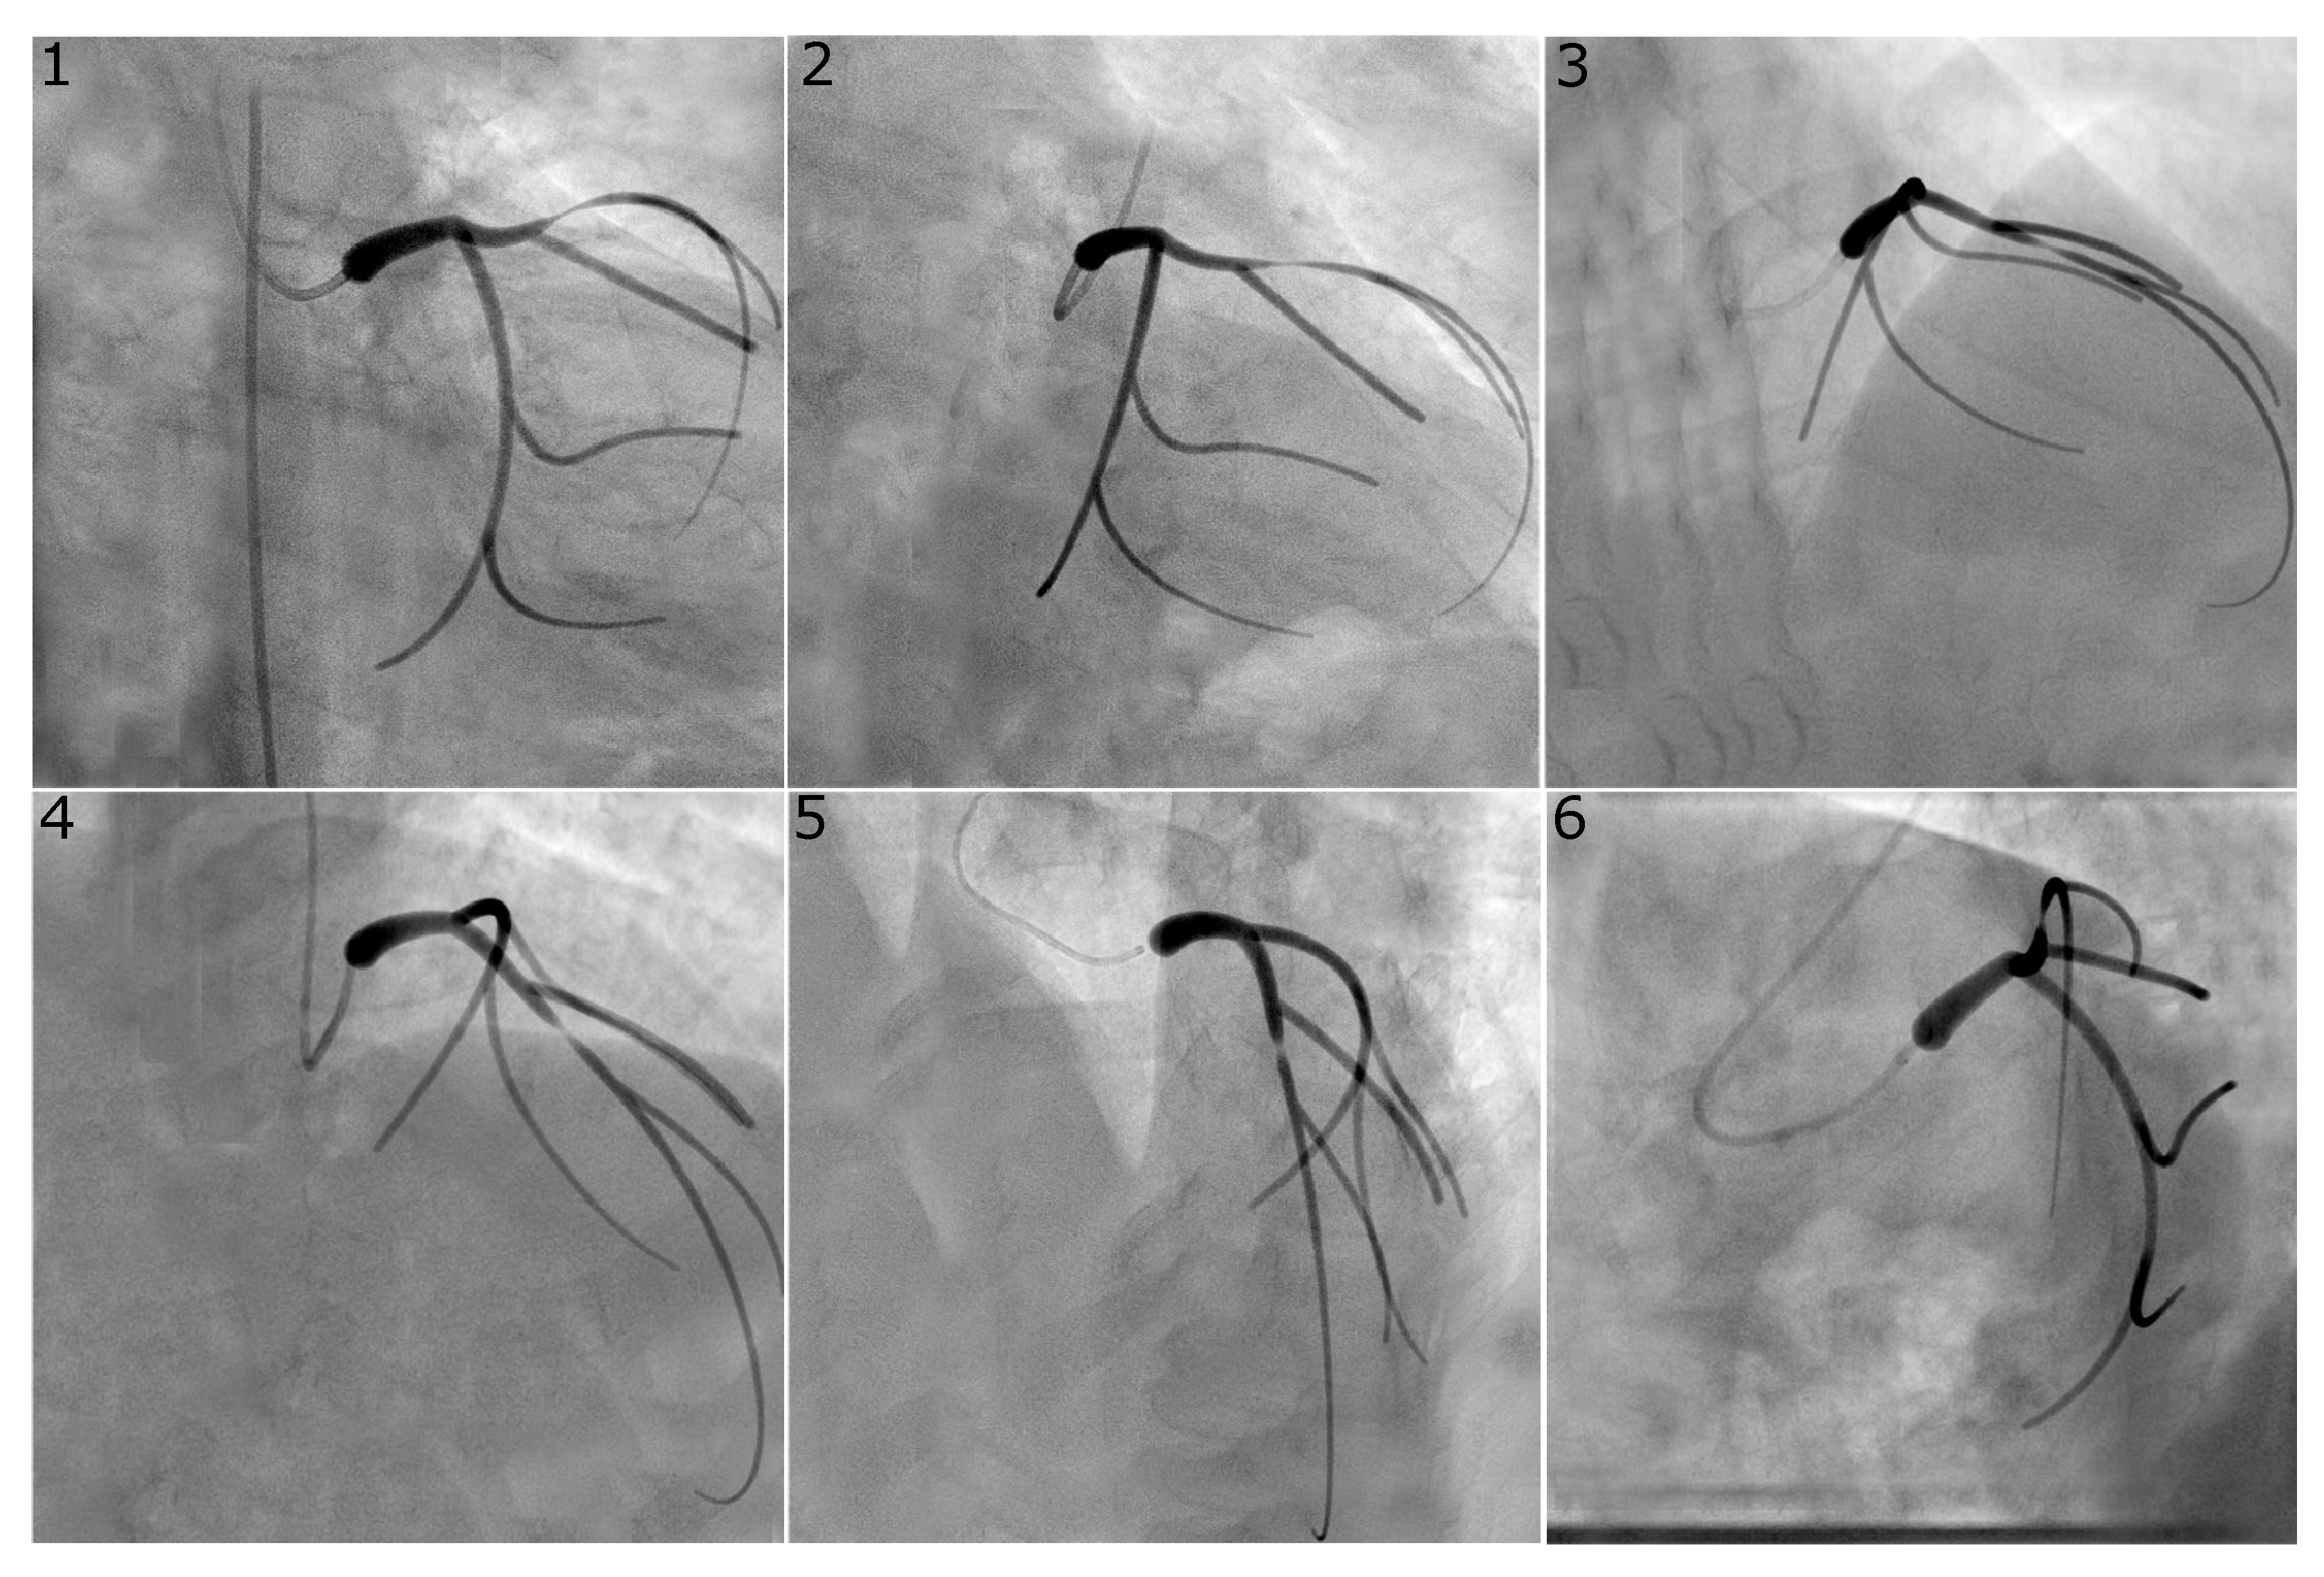

Figure 2.

Virtual angiogram for all views of the left coronary system with a concentric stenosis of diameter reduction in the LCX. Views , and were used to reconstruct this vessel as they are usually selected in the catheterisation laboratory since they avoid vessel overlap and excessive foreshortening for the vessel of interest.

Figure 2 and Figure 3 show representative examples of virtual angiograms generated for the two coronary arteries considered in this study. Figure 2 shows the case in which a concentric stenosis, of diameter reduction, affects the LCX. This case is included here for theoretical interest as it allows for an appreciation of the severity of a stenosis of this diameter reduction, but it is of smaller concern to the clinical community, due to the certainty of its severity. Figure 3 shows the case in which the LAD is affected by stenosis, this time of the eccentric type, with diameter reductions of and in the two orthogonal directions. This case shows how eccentric stenoses can appear differently in different views, and showcases that the choice of the view pair can result in either underestimation or overestimation of the severity of the stenosis (thus, overestimating or underestimating the radius, respectively).